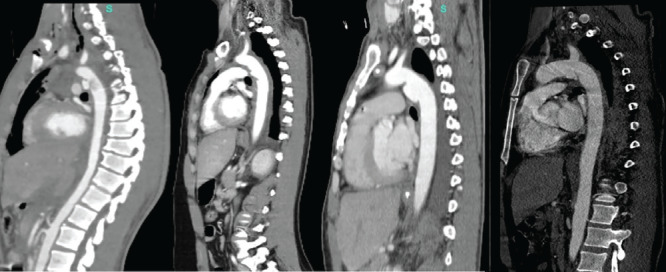

Results: All injuries were caused by high-energy traumas. Mean injury severity score was 38 and the revised trauma score was 6.58. A massive transfusion protocol was activated in 75.0% of cases. Diagnostic imaging showed varying accuracies, with computed tomography demonstrating superior sensitivity for both injuries. All TDH were left-sided posterolateral and BTAI predominantly involved the isthmus. Management followed a sequential approach, with 75.0% of diaphragmatic repairs preceding the aortic intervention. Mean hospital stay was 33 days, with complications including infections, deep vein thrombosis, and atelectasis. Despite the high severity of the injury, all patients survived.

Abstract Image